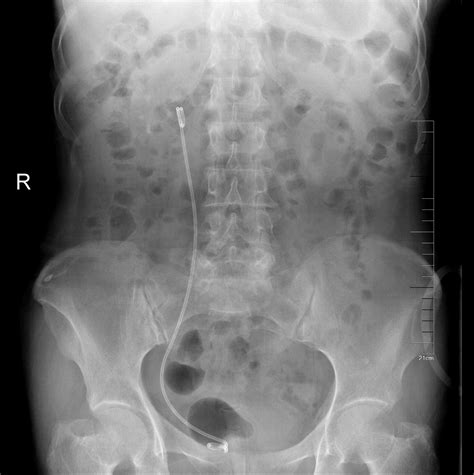

结石手术根据结石所在位置有一下手术方式: 1、输尿管中下段结石考虑行输尿管镜碎石取石术:重庆比较好的医院总费用在1-2万之间 2、输尿管上段结石或肾结石(1.5cm)考虑行经皮肾镜碎石取石术:重庆比较好的医院总费用在2-3万之间

输尿管镜下碎石各家医院收费标准不一样,一般在5-6千,如果不住院(在门诊处理),我们这里大概要3300元,马上处理完及走。

输尿管镜取石术比体外碎石术要痛苦些,价格也高些,但效果要好很多。微创输尿管镜取石术:6000元左右;超声波体外碎石术:1200元左右。